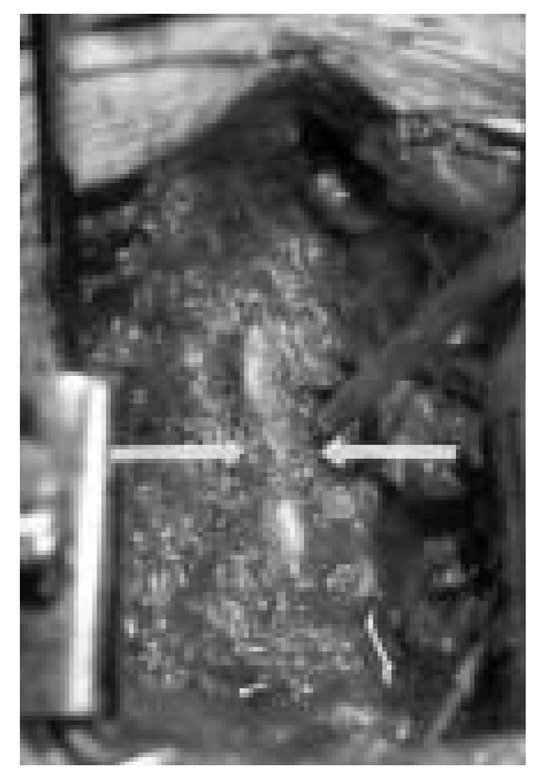

Infiziertes retroperitoneales Hämatom als ungewöhnliche Ursache eines Fallfusses

by R. H. Andres, Alain Barth and R. W. Seiler

Swiss Arch. Neurol. Psychiatry Psychother. 2004, 155(2), 60-63; https://doi.org/10.4414/sanp.2004.01460 - 1 Jan 2004

This is a case report of a 72-year-old woman under oral anticoagulation who presented in the emergency room with a subacute onset of left-accentuated lumboischialgia, a left-side foot drop, a foot plantar flexion palsy and an eversion weakness. Other clinical findings included an [...] Read more.

This is a case report of a 72-year-old woman under oral anticoagulation who presented in the emergency room with a subacute onset of left-accentuated lumboischialgia, a left-side foot drop, a foot plantar flexion palsy and an eversion weakness. Other clinical findings included an abscessing parotitis and an oligoarthritis of unknown aetiology. The neuroradiological evaluation with computer tomography and myeloradiculography did not show any adequate spinal or radicular affection. A complete left-leg palsy and increasing sensory deficits developed during the early course of the hospitalisation. A pelvic CT was performed and revealed a left-sided retroperitoneal mass lesion with compression of the sacral plexus and the ischiadic nerve. CT-guided puncture resulted in the diagnosis of a haematoma infected with Staphylococcus aureus. We considered this process to be induced by the anticoagulant treatment and secondary septic dissemination from the parotid abscess. Percutaneous drainage and antibiotic treatment resulted in fast clinical recovery of the motor deficits; however, mild sensory residues persisted. Our case report demonstrates the necessity to consider for possible extraspinal lesions also in patients presenting with the typical symptoms of radicular compression, particularly when the initial evaluations were not conclusive. Full article

Show Figures

Figure 1